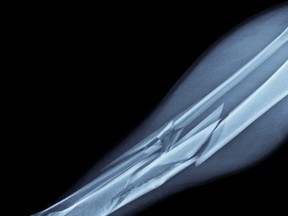

The shin bone, or tibia, is one of two bones in that area of the leg — the other being the fibula, located behind the tibia. Since the tibia holds a significant amount of body weight, it is incredibly strong, especially when compared to the fibula.

Estimates vary on how much force the tibia can take, from just over200 lbs to roughly five times the body weight of its owner. For 136-pound Palencia, this would mean 200-680 lbs of force. Other conditions like previous injuries, the direction of impact and the concentration of the impact over a smaller surface area, all play into how much energy it would take to break this bone.